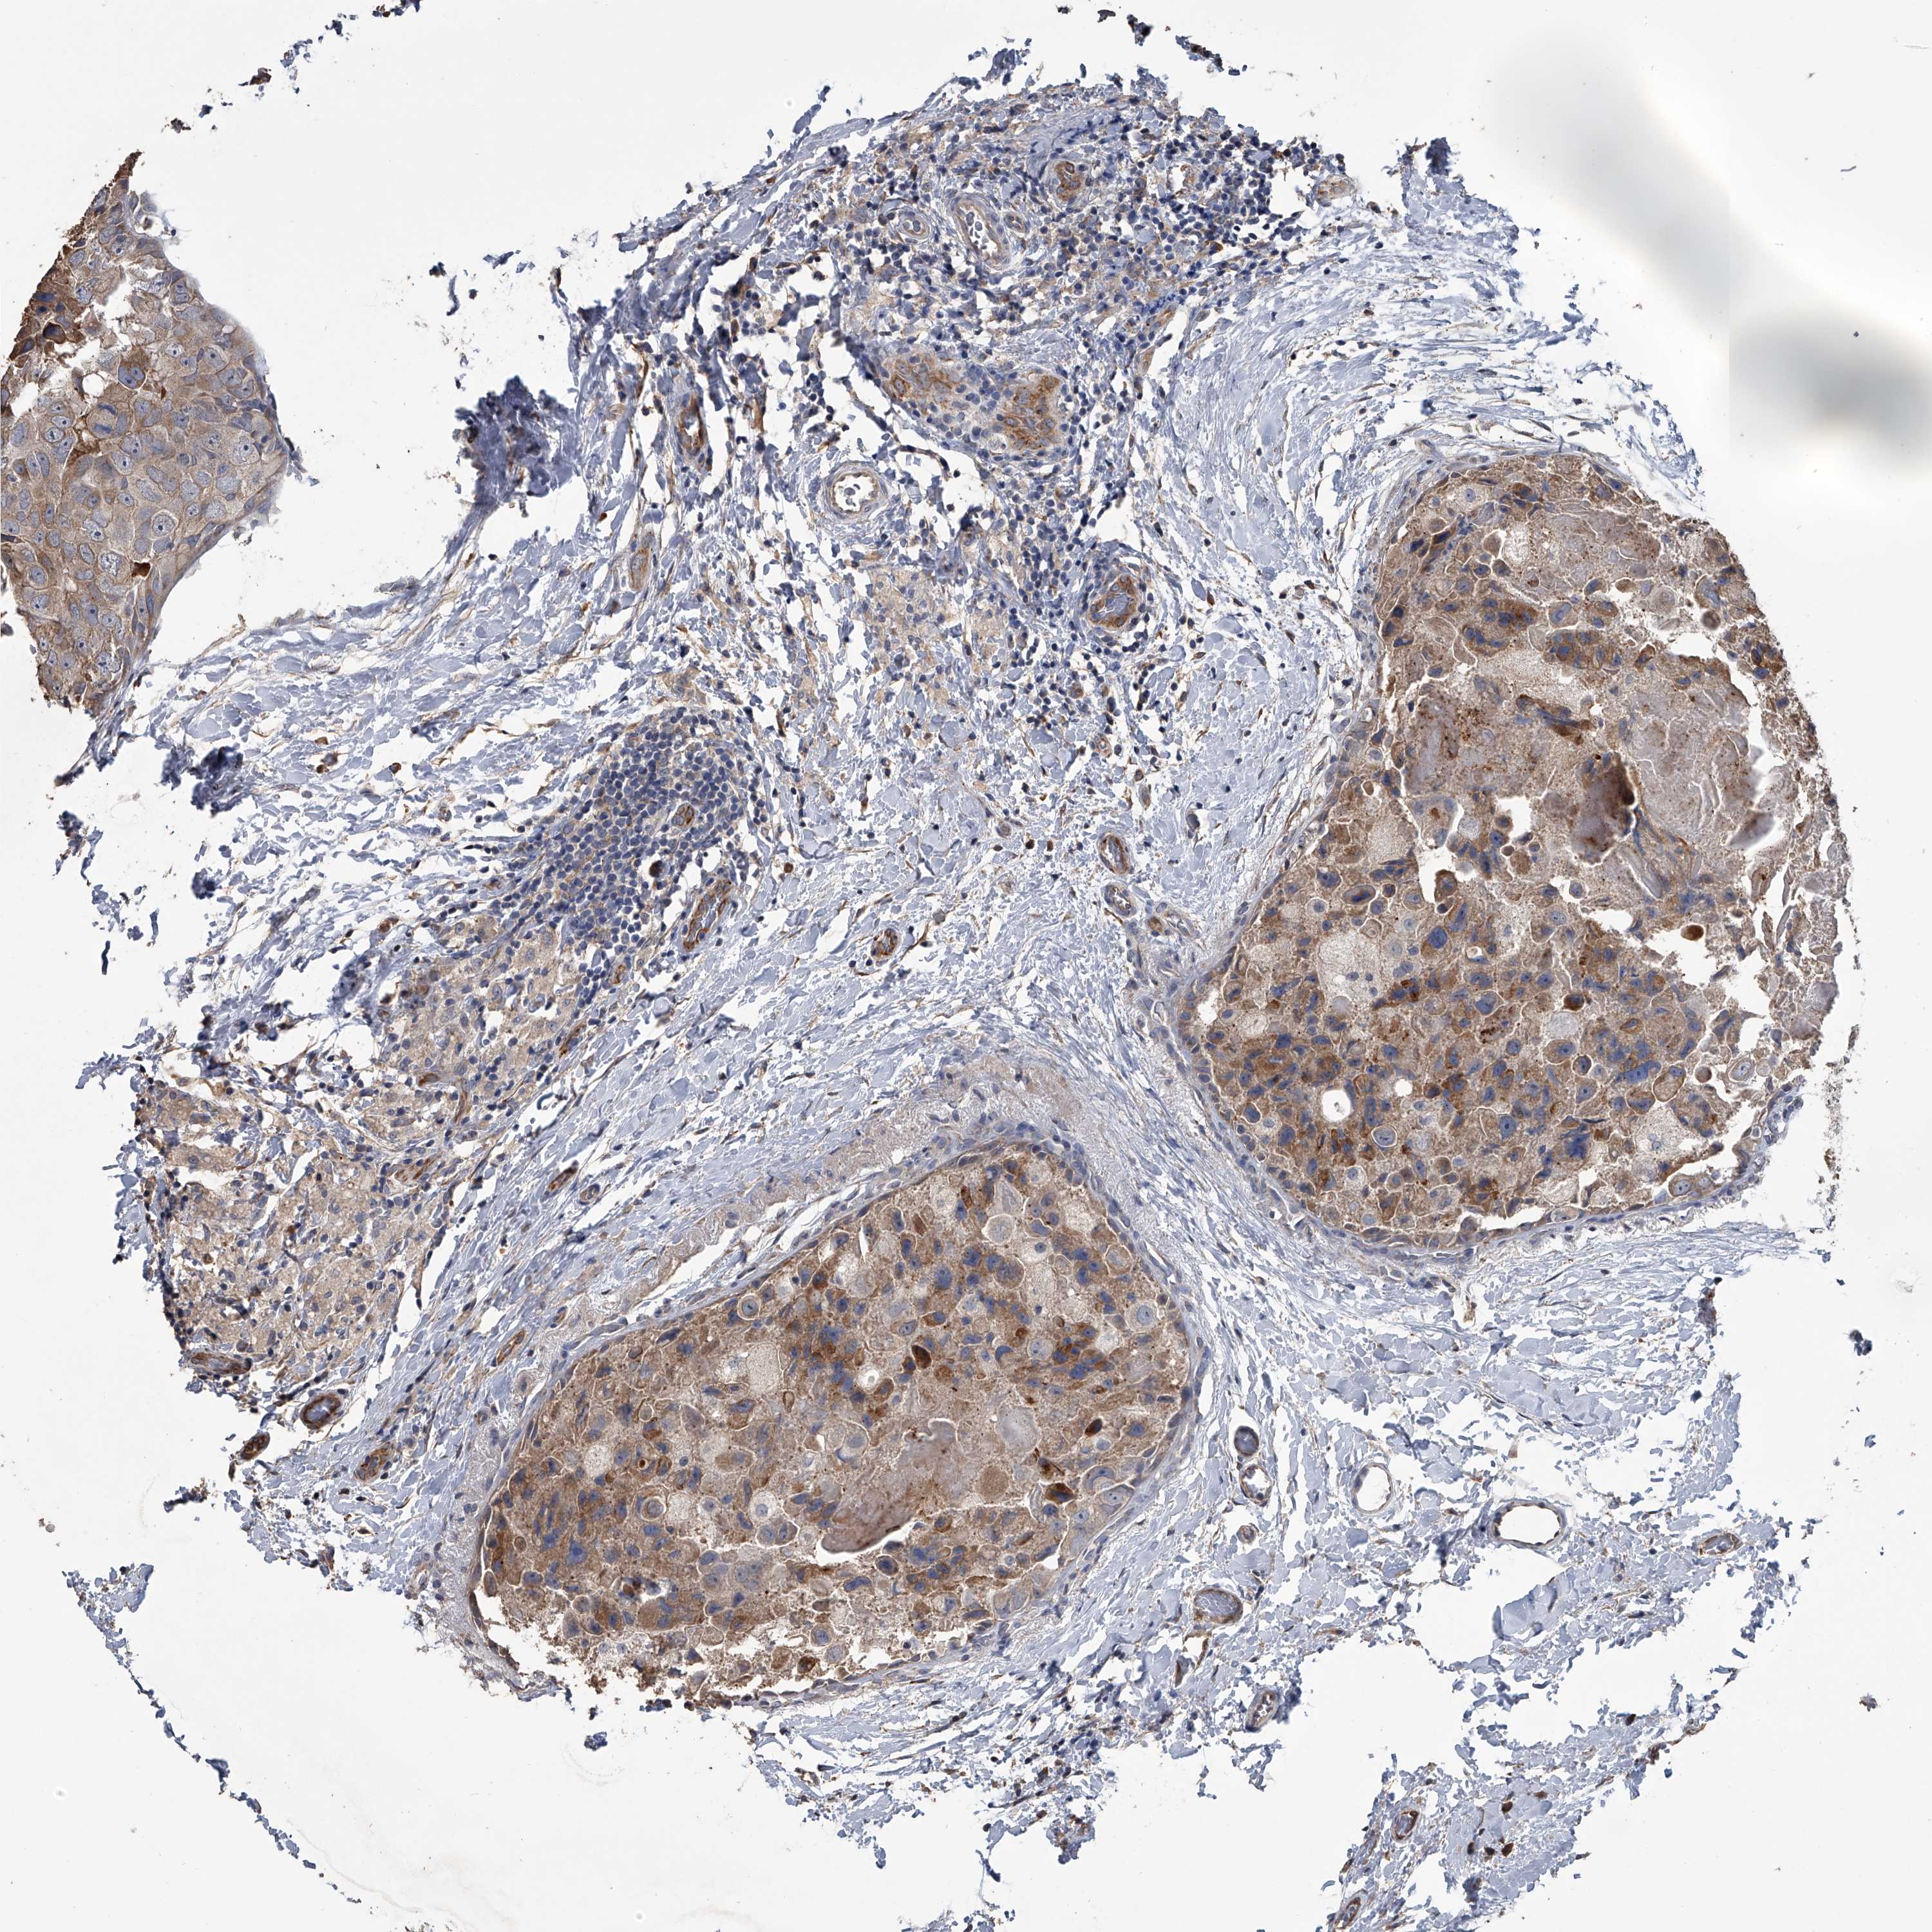

CANCER BREAST CANCER Show tissue menu

BRCA TCGA BRCA VALIDATION PROTEIN EXPRESSION

ANTIBODIES

AND

VALIDATION